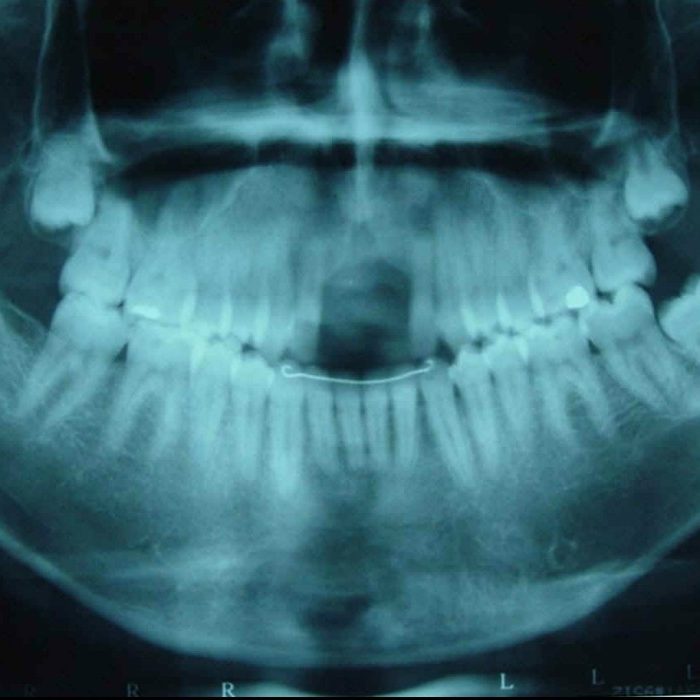

El control de la salud buco-dental es uno de los aspectos menos atendidos en lo referente a la salud integral de los atletas en los servicios dedicados a la medicina del deporte. La salud bucal debe estar siempre presente en un deportista y en mente del grupo de profesionales que lo rodea como parte de…